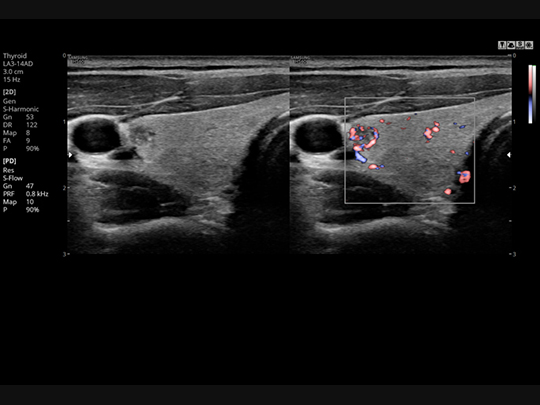

S-Flow™

A sophisticated color Doppler technology with greater sensitivity, S-Flow can detect low-intensity blood flow. It enables accurate diagnosis when blood flow examination is especially difficult.

S-Harmonic™

This new harmonic technology provides greater image uniformity from near to far field while reducing signal noise.

Samsung HS60 Compatible Transducers / Probes

Linear array transducers

LA3-14AD

- Application: abdomen, musculoskeletal, small parts, vascular